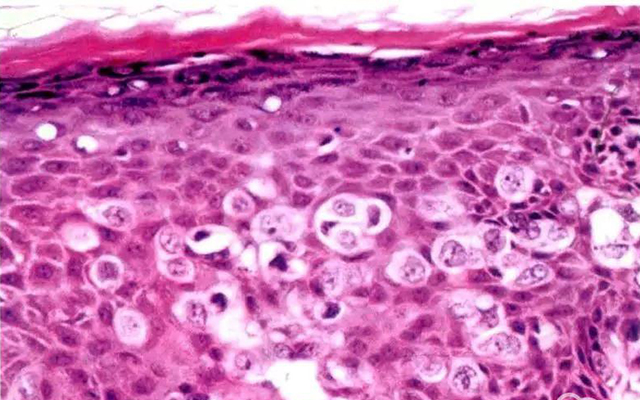

图片来源于网络,侵删

我们常说的过敏大多都有致敏原,比如皮肤瘙痒、*麻疹荨**等,一般表现为皮肤损伤。而过敏性紫癜并不是过敏导致的,它是一种变态反应毛细血管炎,患者一般会在紫癜出现前1-3周有低热、呼吸道感染等表现。

如果还不好理解的话,我们可以把常见的过敏当作是皮肤病,而过敏性紫癜是一种血管炎疾病,两者的发病机制和临床表现截然不一样。

过敏性紫癜的临床表现,除了四肢对称分布的红点红斑皮疹外,还会出现腹痛、恶心呕吐、关节肿痛、小便潜血、尿蛋白等表现。绝大多数患者首发症状是皮疹,而后出现其他表现,也有少部分患者首发症状是腹痛、关节肿痛表现,很容易造成误诊漏诊。